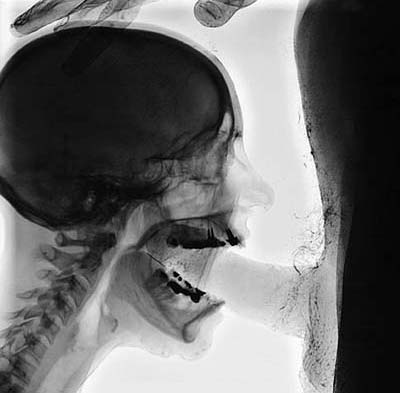

политическим деятелям тоже инди интересны:

картинка взята:

http://rasputin.ru/girl.php?id=9 (страничка инди)

- Вложения

-

- att-414ae64c041d31.jpg (17.91 КБ) 9310 просмотров